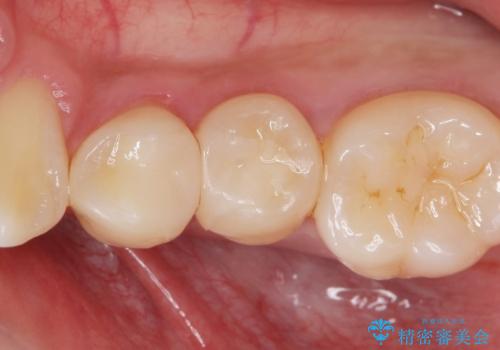

- 矯正前の患者様です。検査により虫歯がありましたのでe-maxインレー治療を行いました。

- e-maxインレー 7.7万×2費用は治療当時の料金となります